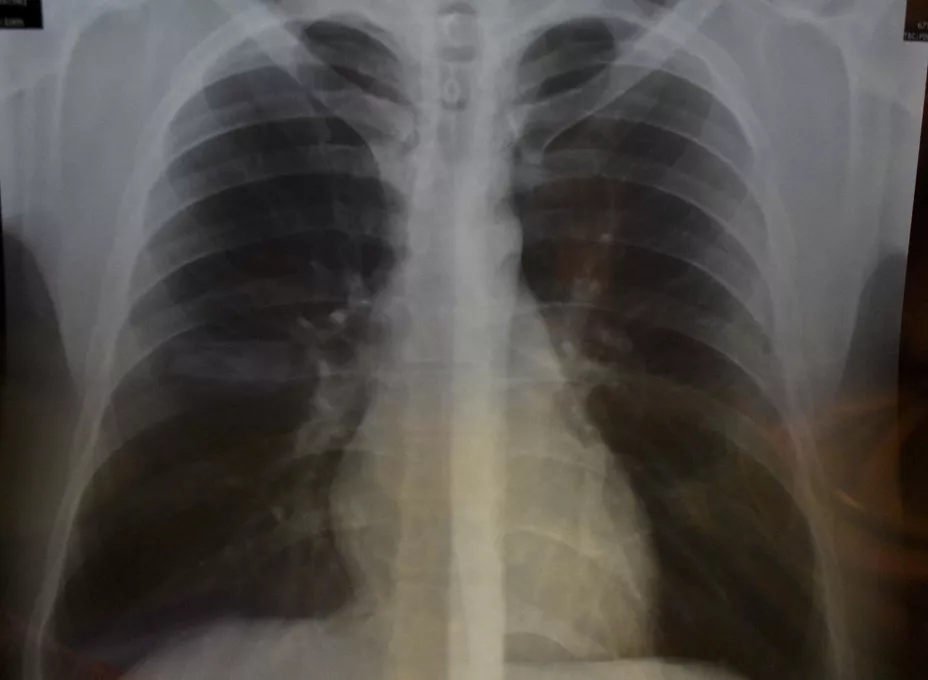

Cifras de la Organización Mundial de la Salud (OMS), señalan que el cáncer de pulmón continúa siendo la neoplasia más agresiva y mortal en el mundo, registrando un incremento en su incidencia del 30% y con 1.69 millones de decesos por año, donde el cáncer pulmonar de células no pequeñas (CPCNP), representa el 80% de todos los casos y ocurre principalmente en las personas de edad avanzada (65 años o más).

A nivel nacional, el cáncer de pulmón se ubica en el séptimo lugar por su frecuencia y ocupa el primer lugar como causa de muerte por cáncer, registrando anualmente más de ocho mil decesos. De acuerdo con el estudio más reciente de Globocan 2018, en el país existen siete mil 811 casos nuevos de CPCNP al año y el 86% de estos pierden la vida, y únicamente entre el 5% y el 8% de los casos es detectado en estadios tempranos, lo que hace necesario implementar medidas para el diagnóstico oportuno.

En México, ocho de cada 10 pacientes con cáncer de pulmón son diagnosticados en etapas avanzadas y ocurre principalmente en las personas de 65 años o más, siendo 70 años la edad promedio al momento del diagnóstico.